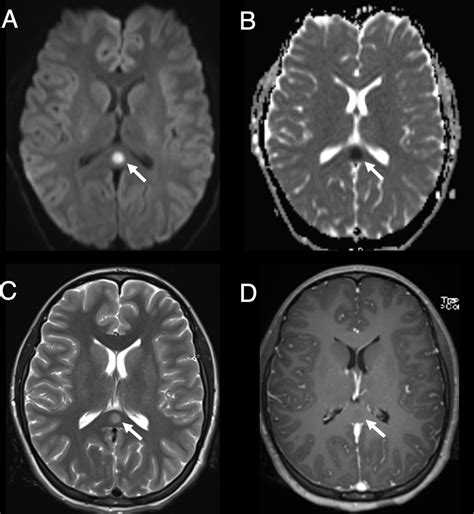

Because the clinical presentation of Toxic Metabolic Encephalopathy mimics many other conditions—such as primary brain tumors, meningitis, or strokes—the diagnostic process is one of exclusion. Doctors must first rule out structural causes of brain dysfunction using imaging like CT or MRI scans.

The outlook for individuals suffering from Toxic Metabolic Encephalopathy depends almost entirely on how quickly the underlying trigger is addressed. In acute, treatable scenarios, patients can often return to their baseline cognitive function with no lasting damage. However, if the metabolic insult is severe or prolonged, there is a risk of secondary damage to the brain, which may manifest as persistent cognitive deficits or structural changes on follow-up imaging.

• toxic metabolic encephalopathy radiology